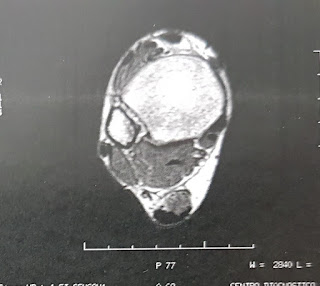

Le pido una RM en T1 y T2 en todos los cortes posibles y entonces descubrios el por qué de su dolor.

El paciente presentaba una gran tumoración en Seno del Tarso con migración superoexterna, cambios degenerativos en el Tendón de Aquiles y degeneración de la fascia plantar en su inserción.